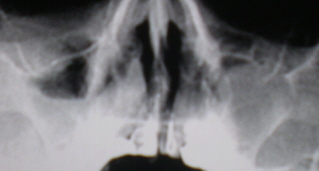

На снимках регистрируется окаймляющая стенки пазухи плотная тень шириной от 0,3 до 0,5 см и более, которая отлича­eтcя от таковой при остром процессе не только шириной, но и стойкостью. При динамическом наблюдении эта тень не исчезает – иллюстрации 8 и 9.

На иллюстрации 8. Определяется снижение прозрачности лобной пазухи довольно однородной структуры с локальным утолщением её над правой орбитой. Справа определяется пристеночное снижение прозрачности гайморовой полости с не четким и неровным контуром, особенно базально. Слева определяется субтотальное снижение прозрачности, с выраженным пристеночным снижение прозрачности вдоль верхней стенки.